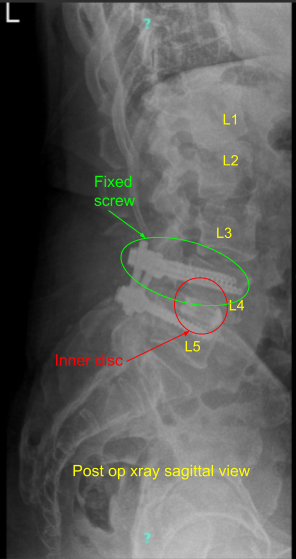

A small BMP was opened in preparation for the fusion. Revision decompression of the L4-5 was performed with inferior laminectomy of the L3. The bone was used for local autograft. A thorough decompression of the L4 and L5 of the left and right was performed with the use of curettes followed by Kerrison punch. Full decompression could be achieved. A new set screw was put on to the left L4 and torqued in the usual fashion.

Final pictures were taken and saved. The wound was thoroughly irrigated. One-fourth of the small BMP strip was used and put on the right side followed by autograft and cancellous chips to achieve fusion. The wound was thoroughly irrigated and draped. Hemostasis was achieved with the use of Bovie,

Patient’s next office visit was one week status post L3-5 decompression and L4-5 PSF with improving neurologic involvement (urinary incontinence). Patient was followed in our office on regular intervals of 2 weeks, 6 weeks, 3 months and 6 months thereafter with gradual return of function. Physical therapy was also started. Patient did well postoperatively